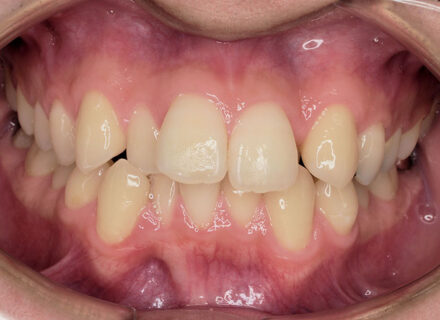

受け口、反対咬合の治療写真 前歯部に叢生(がたつき)がある、受け口、前歯反対咬合の患者さんです。 虫歯の処置歯が多いだけでなく…